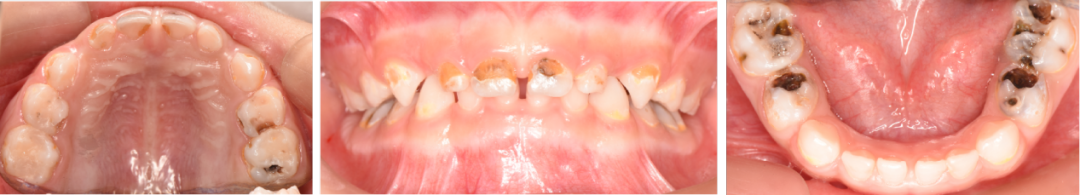

小邓口腔治疗前的照片